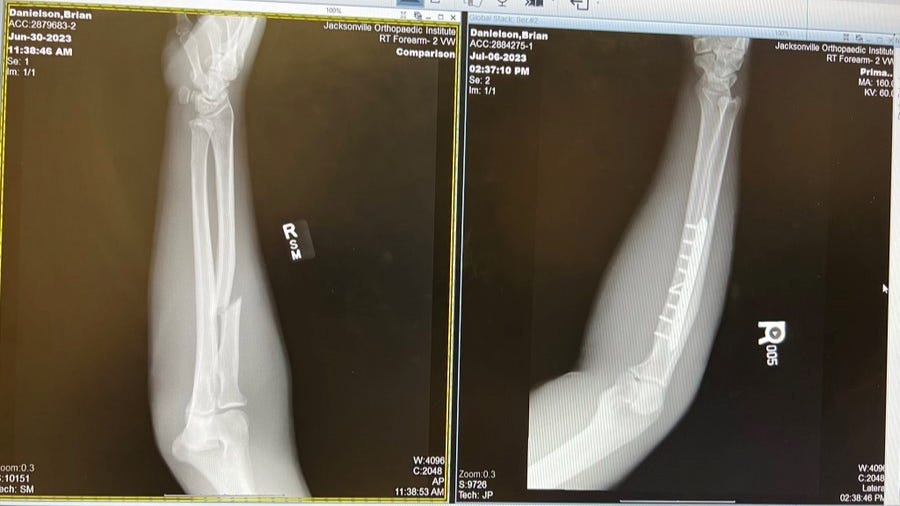

Bryan Danielson provided an update to his arm injury on Twitter yesterday, revealing he underwent surgery two weeks ago to repair the broken arm.

Danielson posted x-ray pictures and revealed doctors put a steel rod and nine screws in his arm.